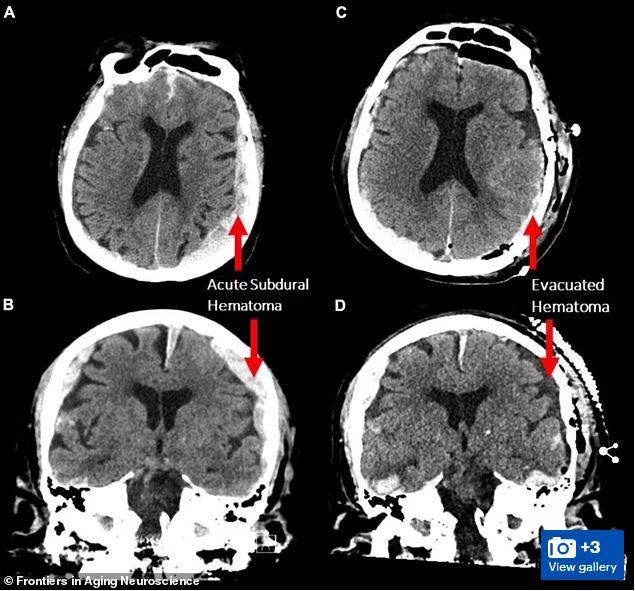

![[서울=뉴시스]죽기 직전 지난 삶의 중요한 순간들이 주마등처럼 머리 속을 스쳐 지나간다는 말이 사실일 수 있음을 시사하는 과학적 증거가 우연히 포착됐다고 BBC가 23일(현지시간) 보도했다. 한 과학자 팀이 뇌전증(간질)에 걸린 87세 환자의 뇌파를 측정하던 도중 이 환자가 예상치 못하게 심장마비를 일으켜 사망하면서 그의 뇌파가 약 30초 가량 꿈을 꾸거나 기억을 떠올리는 것과 같은 패턴을 따른다는 사실이 밝혀졌다. <사진출처 : 데일리 메일> 2022.2.24](https://img2.daumcdn.net/thumb/R658x0.q70/?fname=https://t1.daumcdn.net/news/202202/24/newsis/20220224071902881jqcc.jpg)

연구팀은 22일에 발간된 '노화 신경과학 프론티어스(Frontiers in Noing Neuroscience)'에 실린 연구에서 이런 종류의 뇌 활동은 사람의 마지막 순간에 일어날 수 있다는 것을 암시한다고 밝혔다.

젬마 박사팀은 그러나 단 하나의 연구만으로 광범위한 결론이 도출될 수는 없다고 경고했다. 특히 환자가 뇌전증이었고, 출혈이 있고, 뇌가 부어 있었기 때문에 상황은 더욱 복잡하다. 젬마는 "단 한 가지 사례만으로 이 같은 보고를 하는 것이 결코 편하지 않다. 2016년 최초 (뇌파)촬영 이후 비슷한 사례를 찾아봤지만 성공하지 못했다"고 말했다.